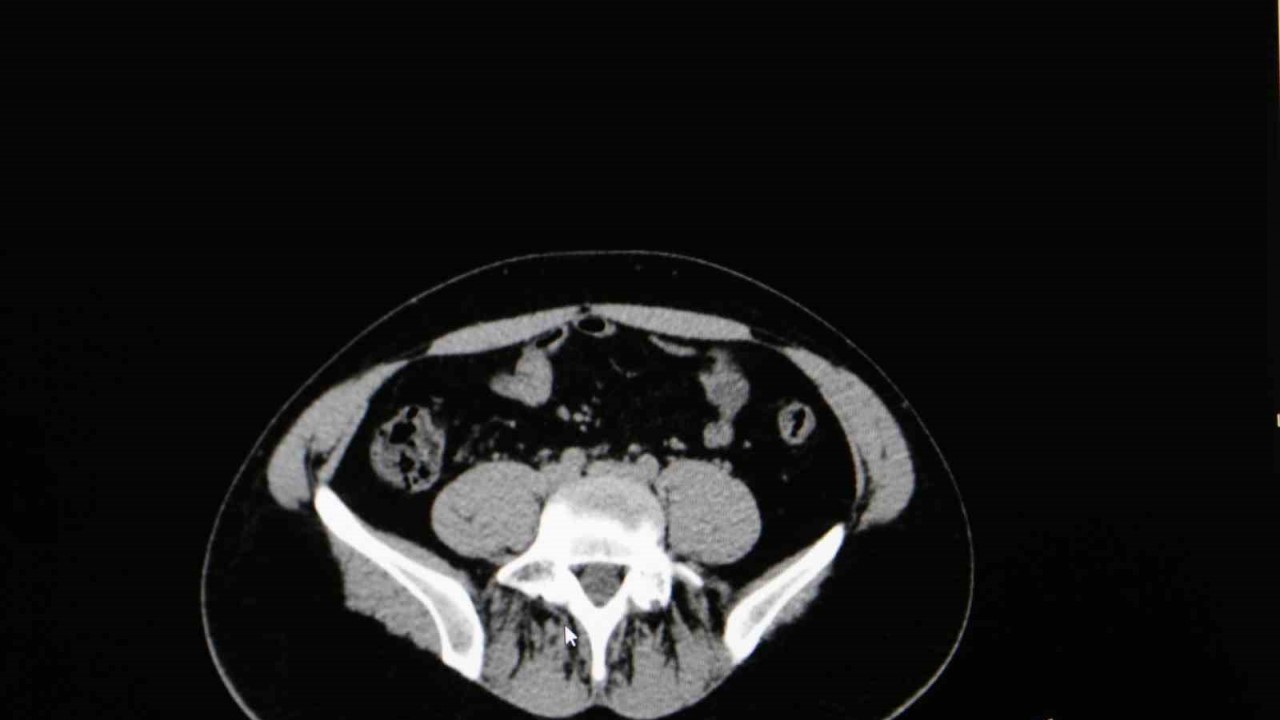

Diyarbakır Dicle Memorial Hastanesi’nde görev yapan Üroloji Uzmanı Op. Dr. Birgi Ercili “Sistit, aslında idrar torbası dediğimiz mesanenin iltihabıdır. Daha çok enfeksiyon sebepleriyle oluşur. Sistin daha çok sebebi idrar yoluna genital bölgeden ulaşan mikroorganizmalardır. Özellikle kadınlarda sistit dediğimiz durum çok fazla görülür. Çünkü kadınlarda üretra dediğimiz idrar yolu, erkeklere göre oldukça kısadır. Vajina ve anüse yakın olduğu için oradan gelen mikroorganizmaların idrar yolu aracılığıyla mesaneye ulaşması daha kolaydır. Kadınların yarısı hayatlarında muhakkak en az bir defa bu hastalığı geçirmektedir” ifadelerine yer verdi.

Sistitin sık görülen belirtilerinden idrar yanması ve az idrar yapma olduğunu ifade eden Ercili, “Sistit geliştiğinde özellikle idrarda yanma, sızı, sık sık ve az idrar yapma, damla damla idrar yapma, kasık ve alt karın bölgesinde ağrı, idrarda kan ve bulanık idrar görülebilir. Bazen de kadınlarda ilişki sonrası ağrı görülebilir. Genital hijyene çok dikkat edilmemesiyle, tuvalet temizliğini arkadan öne doğru yapılmasıyla mikropların idrar yoluna daha hızlı şekilde ulaşabildiğini görmekteyiz. Bunların dışında nemli çamaşırlarla beklemek, sık çamaşır değiştirmemek, az sıvı almak sistite sebep olabilmektedir. İlişki sonrasında da yine idrar yolunda tahriş meydana geldiği için sistit durumlarını görebilmekteyiz” diye konuştu.

Sistit tedavisinde bol sıvı tüketilmesi gerektiğine dikkat çeken Ercili, şunları kaydetti:“Hastanın şikayetlerini dinledikten sonra basit bir idrar tahliliyle sistit tanısını rahatlıkla koyabiliyoruz. Tedavisinde de genelde kısa süreli 5 gün kadar kullanılan ağızdan bir antibiyotik tedavisiyle rahatlıkla tedavi edebiliyoruz. Bunun yanında mutlaka bol sıvı almak da tedavinin önemli bir parçasını oluşturmaktadır.”